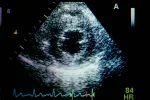

Pero cuando los síntomas no son controlados con facilidad mediante fármacos, el ventrículo empieza a dar síntomas de insuficiencia o existe desestructuración del aparato valvular como consecuencia de una endocarditis, debe plantearse la intervención quirúrgica como tratamiento definitivo. Este consiste en la reparación de la válvula conservando en lo posible el resto del aparato valvular, ofreciendo así un mejor pronóstico aun a costa de dejar un cierto grado de insuficiencia valvular, pero con una disminución notable de los síntomas.

En otros casos se procede a la sustitución total de la válvula y del resto de estructuras del aparato valvular, que implica una mayor complejidad quirúrgica, y necesidad de anticoagulación de por vida si la sustitución es por una válvula metálica. La posibilidad de implantar una válvula biológica (de cerdo) también es una opción quirúrgica, que no implica anticoagulación, pero con fecha de caducidad pues estas válvulas también se degeneran con el paso de los años.